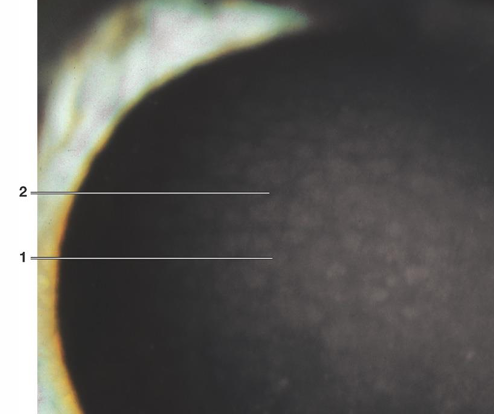

Corneal Arcus

Description: Common age-related lipid degeneration of the peripheral cornea. Occurs in stromal layer

Bilateral condition.

Lipid deposits initially in the inferior cornea, then superior, and eventually circumferential.

Appears as a roughly 1mm wide whitish band in the peripheral cornea.

A clear interval exists between the arcus and the limbus (lucid zone or lucid interval of Vogt).

Possible mild non-progressive thinning of the clear marginal zone.

Sharp outer outline with a diffuse central boundary.

Symptoms: Usually asymptomatic, requiring no treatment.